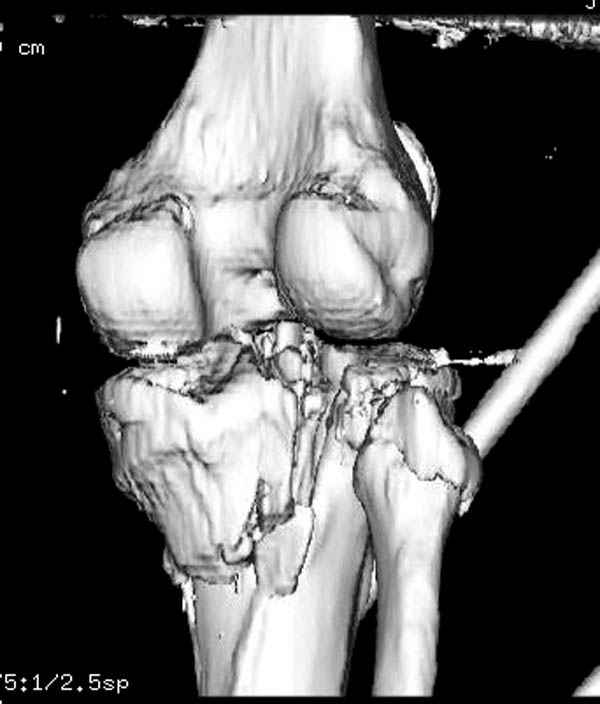

Здесь как раз тот случай, когда результат зависит не только от мастерства хирурга, но и от наличия современных методов исследования. Например, КТ которая поможет рассчитать направления шурупов и установку импланта. Кроме этого, поможет определиться с доступом.

На представленных предоперационных срезах КТ огромный задне-медиальный фрагмент расположен больше кзади, чем медиально. Для планирования, кроме поперечных срезов, надо ориентироваться на корональные срезы, которые укажут топографию верхушки медиального фрагмента.

Надеюсь, представленные снимки разных случаев помогут разобраться в тактике, и критика примется без личной обиды.